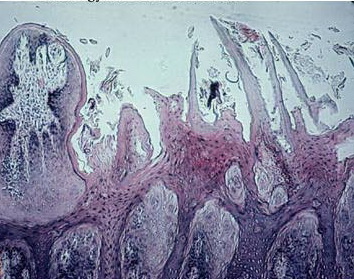

Read MoreSeborrheic keratosis, acanthotic type = التقران الدهني من النموذج الشواكي Seborrheic Keratosis Seborrheic keratoses are very common: sometimes single but often multiple. They occur mainly on the trunk and face but also on the extremities, excluding palms and soles. They usually do not appear before middle age, but are present in about 20% of the […]